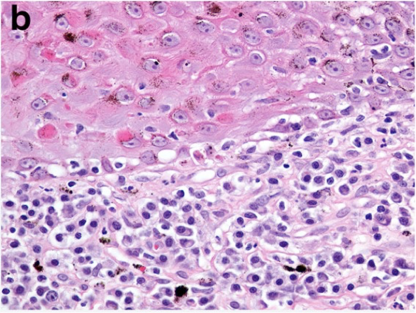

How does discoid lupus erythematous present histologically?

Sub-epidermal lymphoplasmacytic dermatitis (interface dermatitis)

Pigmentary incontinence (basal cell damage = melanin no longer held well)